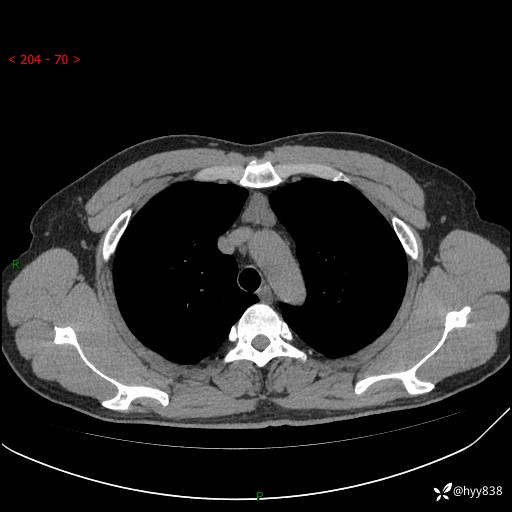

患者性别:女

患者年龄:49岁

简要病史:跟骨骨折,常规CT发现纵隔占位

胸部CT平扫